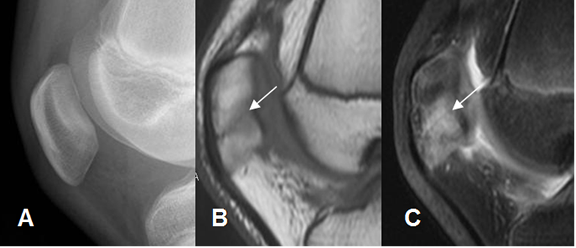

Fig 53. Fractura de patela.

A: Rx lateral de rodilla. No se encuentran anormalidades.

B: RM sagital en T1 y C: RM sagital en STIR. Edema óseo, con fractura lineal y en sentido oblicuo.